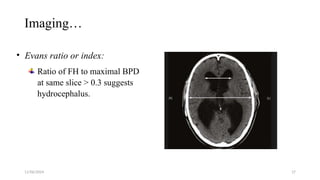

Imaging…

• Evans ratio or index:

Ratio of FH to maximal BPD

at same slice > 0.3 suggests

hydrocephalus.